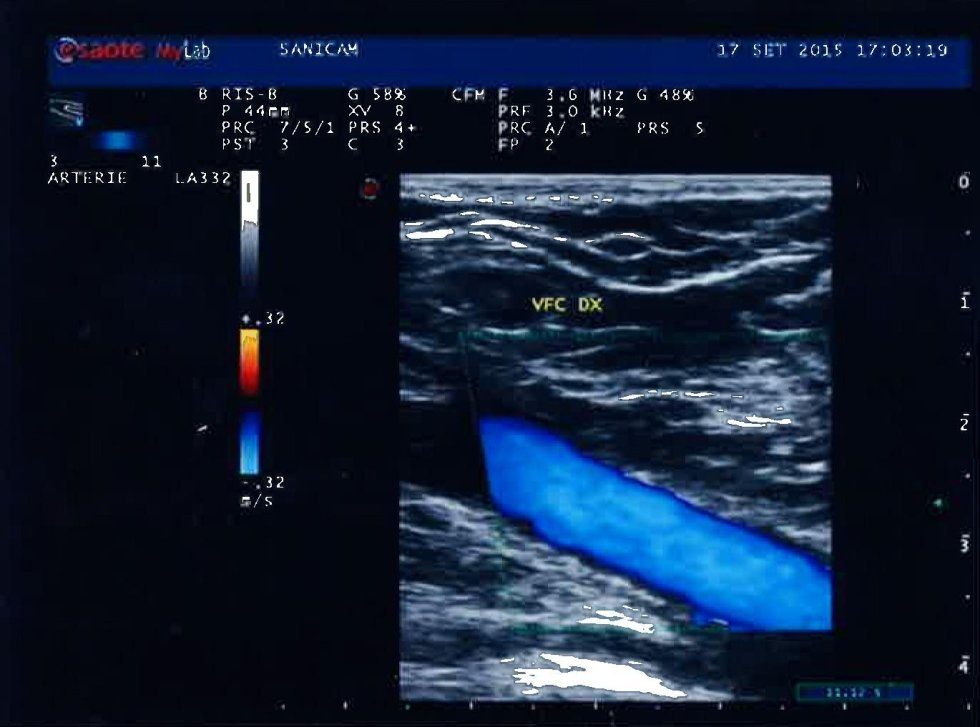

L' eco color doppler dei distretti arterioso e venoso degli arti inferiori

è necessario in caso di insufficienza venosa, varici, trombosi venose o in quei casi di dolore agli arti inferiori, insorgente con la deambulazione.